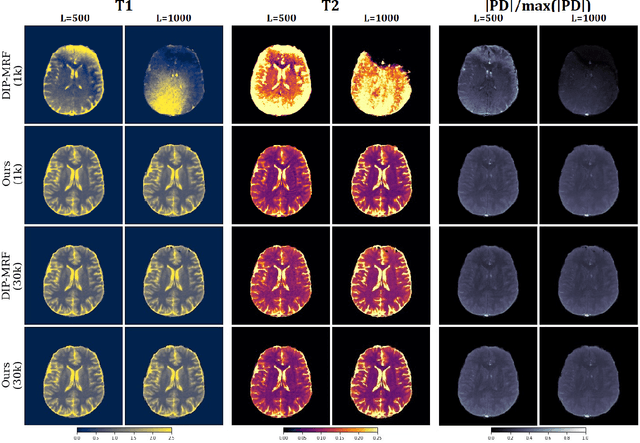

Abstract:The estimation of multi-parametric quantitative maps from Magnetic Resonance Fingerprinting (MRF) compressed sampled acquisitions, albeit successful, remains a challenge due to the high underspampling rate and artifacts naturally occuring during image reconstruction. Whilst state-of-the-art DL methods can successfully address the task, to fully exploit their capabilities they often require training on a paired dataset, in an area where ground truth is seldom available. In this work, we propose a method that combines a deep image prior (DIP) module that, without ground truth and in conjunction with a Bloch consistency enforcing autoencoder, can tackle the problem, resulting in a method faster and of equivalent or better accuracy than DIP-MRF.